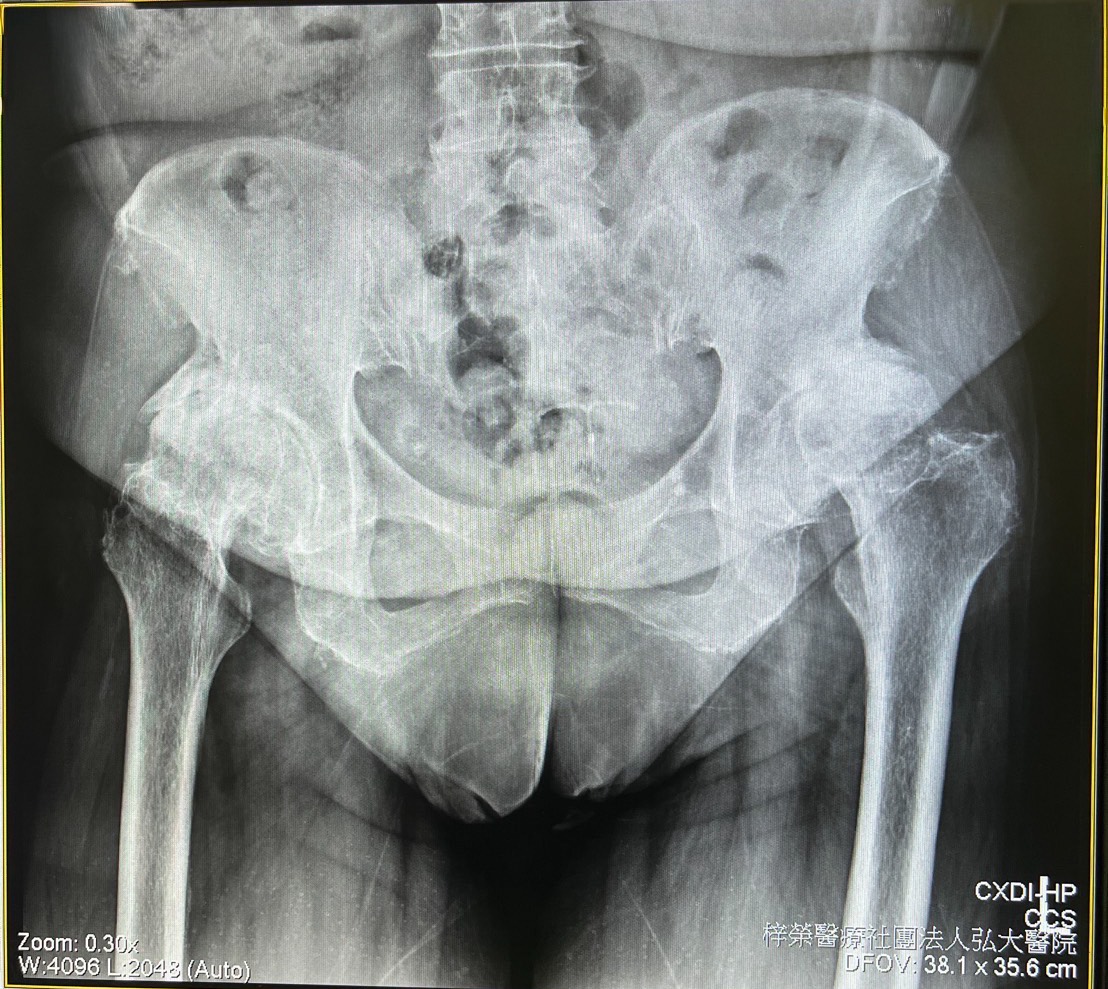

三週前患者前來弘大醫院劉有漢院長門診。劉院長經過詳細理學檢查與影像檢查後,確認人工膝關節並無問題,真正的原因出現在髖關節:雙側髖關節僵直、活動受限,X 光顯示髖關節已嚴重變形,屬於末期髖關節炎。因此,劉院長建議病人接受人工髖關節置換手術。

圖2. 兩髖關節呈現嚴重關節病變